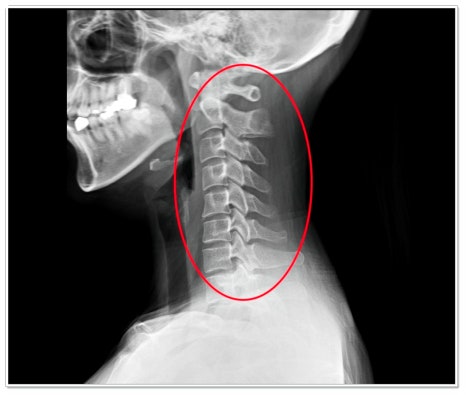

거북목, 일자목, 라운드 숄더는 현대인에게 매우 흔한 체형 문제입니다.

이 세 가지는 사실 서로 긴밀하게 연결되어 있죠.

이때 어깨 관절과 견갑골의 위치가 어긋나면서 상체의 균형이 무너지게 됩니다.

이렇게 굳어진 자세는 근육 불균형을 유발해, 교정이 점점 어려워집니다.

단순한 스트레칭만으로는 근본적인 개선이 어려운 이유가 바로 여기에 있습니다.